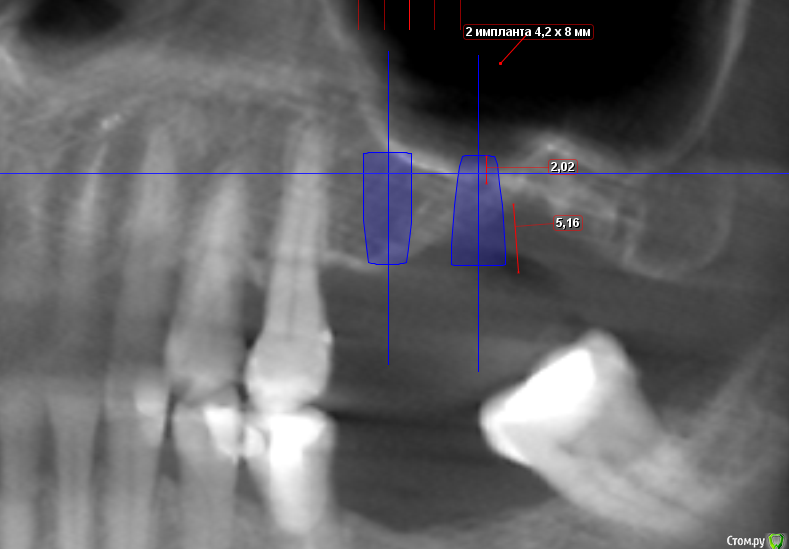

Sergiosse Опубликовано 20 января, 2016 Поделиться Опубликовано 20 января, 2016 Планируется установка 3 - х имплантов .В обл. 16 зуба 4,2х10мм ,на 2,5мм выходит в синус.Планирую подломить стенку остеотомом и вкрутить. В обл 26зуба 4,2х8мм.тоже самое. А с 27 что делать? Зуб удален 2.5 мес. назад.Посоветуйте, как поступить? Заранее спасибо. Ссылка на комментарий